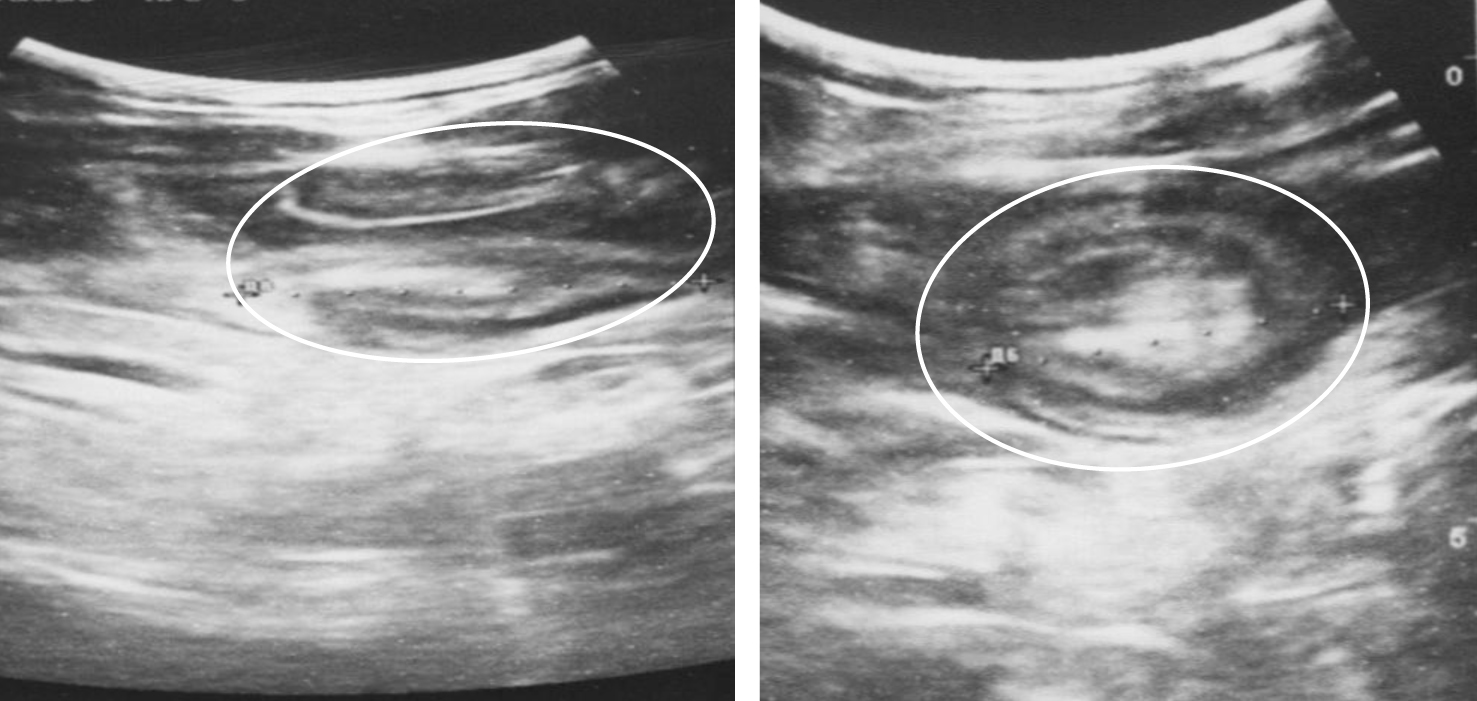

Диагностическая ценность, чувствительность и специфичность методов диагностики ООТК в экстренной ситуации и при плановом обследовании различны [11, 12]. Обзорная рентгенография позволила выявить свободный газ в брюшной полости у 10 из 12 пациентов (83,3 %) с перфорациями тонкой кишки и перитонитом. Еще у двух больных прикрытые перфорации были выявлены во время лапаротомии. Ультразвуковое исследование на фоне кишечной непроходимости (n = 51) позволило выявить ОТК у 20 пациентов (39,2 %), при этом у 17 пациентов (33,3 %) в стенке кишки были визуализированы гипоэхогенные, однородные, преимущественно внутриполостные структуры с ее утолщением и деформацией (рис. 2), признаки инвагинации у 3 (5,9 %) (рис. 3). У 31 пациента ОТК как причина ОКН выявлена не была (60,8 %).

Рис. 3. Ультразвуковая картина инвагинации, инвагинат отмечен белым контуром